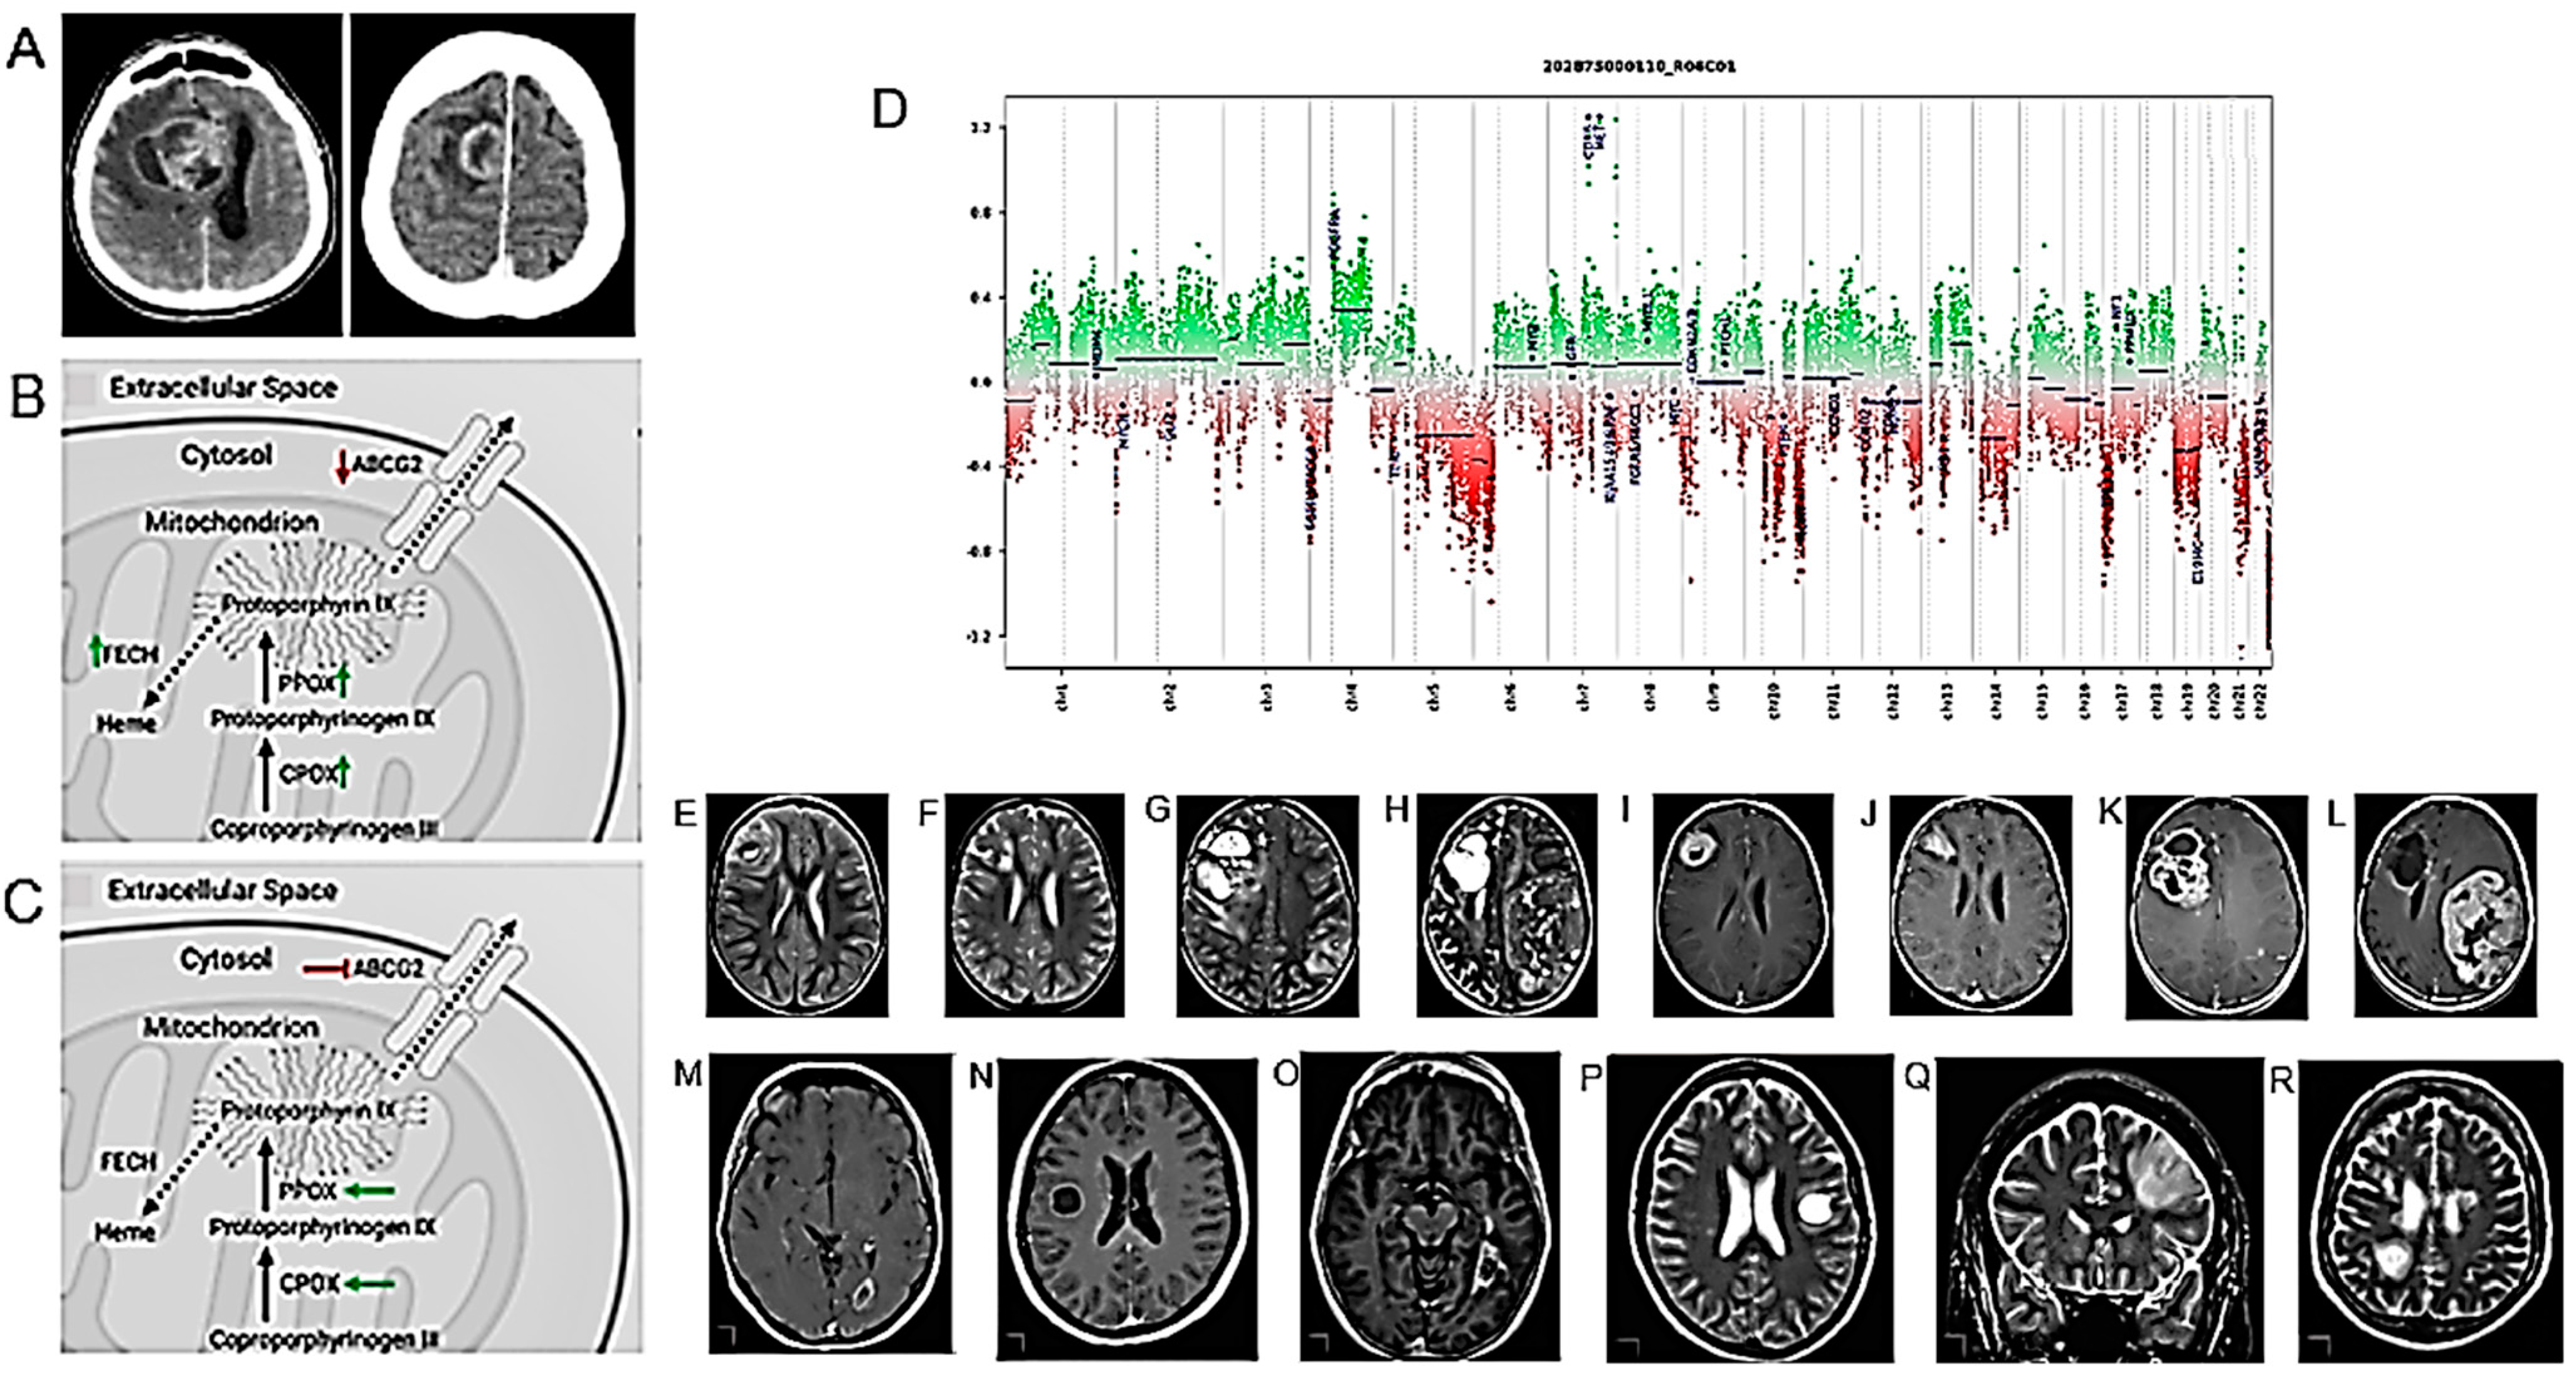

| Intramitochondrial heme biosynthesis factors as pharmacological targets to enhance intraoperative 5-ALA fluorescence visualization. | 19 strongly fluorescing and 21 non-fluorescing tissue samples from neurosurgical adult-type diffuse gliomas (WHO grades II–IV). | [80] |

| Grade-specific cerebrovascular dysregulation in the entire brain of glioma patients. | 96 patients with histologically confirmed cerebral glioma. | [81] |

| rs-fMRI may identify neural correlates for cognitive and daily functioning in glioma patients. | 22 patients with diffuse gliomas who completed treatment within the past 10 years. | [110] |

- Mischkulnig, M.; Roetzer-Pejrimovsky, T.; Lötsch-Gojo, D.; Kastner, N.; Bruckner, K.; Prihoda, R.; Lang, A.; Martinez-Moreno, M.; Furtner, J.; Berghoff, A.; et al. Heme Biosynthesis Factors and 5-ALA Induced Fluorescence: Analysis of mRNA and Protein Expression in Fluorescing and Non-Fluorescing Gliomas. Front. Med. 2022, 9, 907442. [Google Scholar] [CrossRef]

- Cai, S.; Shi, Z.; Zhou, S.; Liang, Y.; Wang, L.; Wang, K.; Zhang, L. Cerebrovascular Dysregulation in Patients with Glioma Assessed with Time-Shifted BOLD fMRI. Radiology 2022, 304, 155–163. [Google Scholar] [CrossRef]